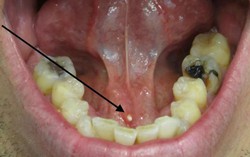

Sỏi tuyến nước bọt dưới lưỡi: Nguyên nhân, triệu chứng và cách điều trị

Phòng & chữa bệnh 10:10 18/07/2024Sỏi tuyến nước bọt có thể gây đau và sưng miệng, nghiêm trọng hơn có thể gây nhiễm trùng.